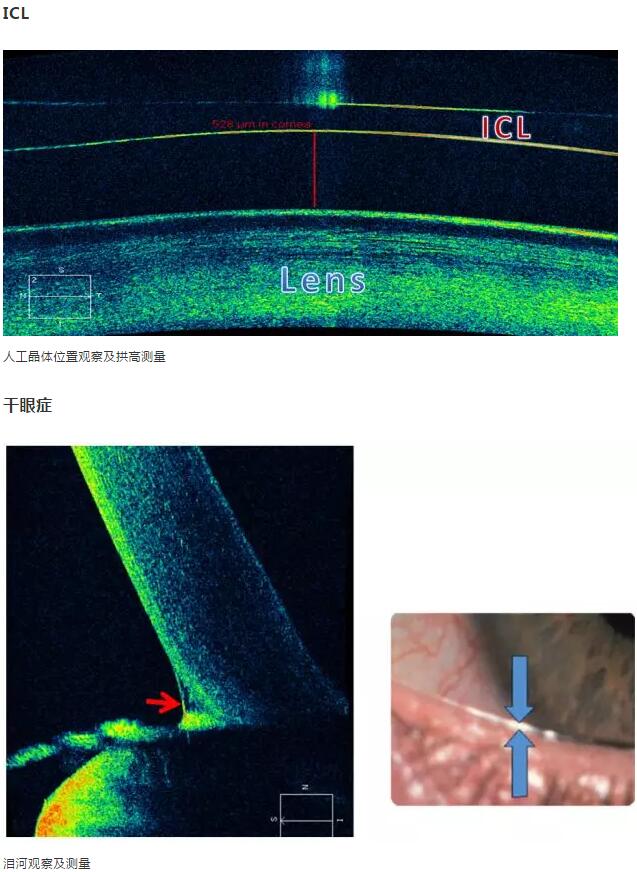

那么接下来,再来分别展示下角膜病、青光眼、白内障、干眼症等疾病的前节OCT检查运用吧!

2、角膜厚度评估,角膜水肿、瘢痕、混浊、溃疡、异物、炎症、胬肉等断层观察